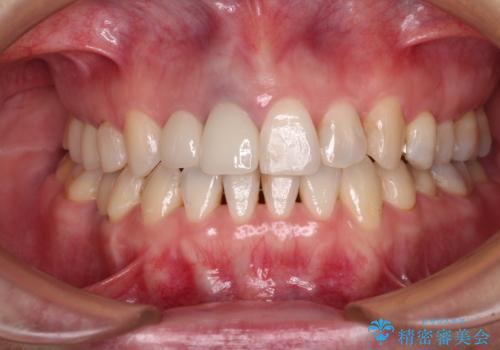

前歯の反対咬合をワイヤー矯正で改善して噛みやすく